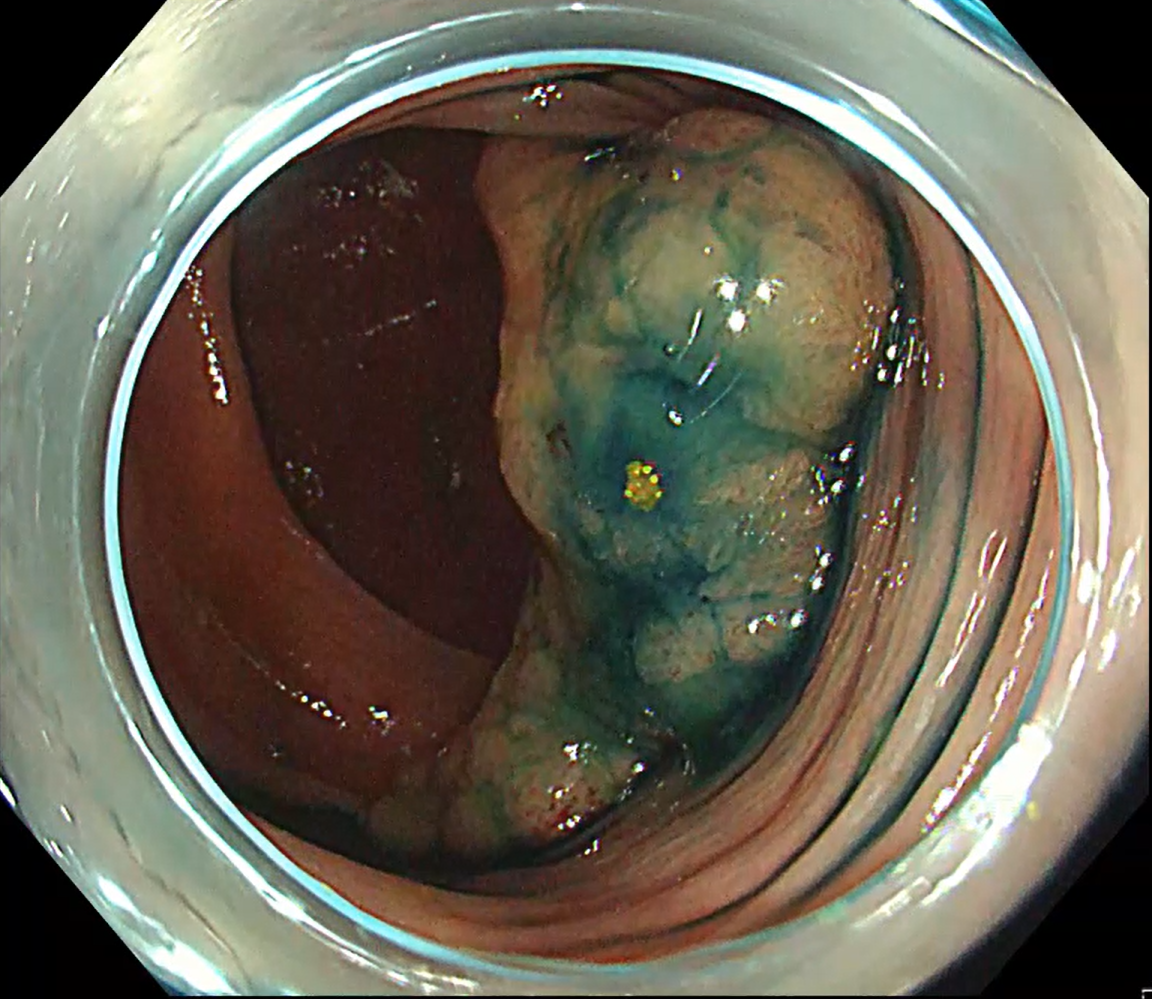

A 50 mm laterally spreading tumour in the ascending colon was addressed (Fig. 13). With ITknife nano the fundamental manoeuvre is “inside to outside”, advancing toward the lumen (Fig. 14).

Even when a large vessel or ambiguous fold obscured the plane, safe dissection was possible by first creating a small ‘hold’ on the vessel side – lightly melting the blue submucosa with the insulated tip – then continuing the inside to outside approach (Fig. 15, Movie 3).